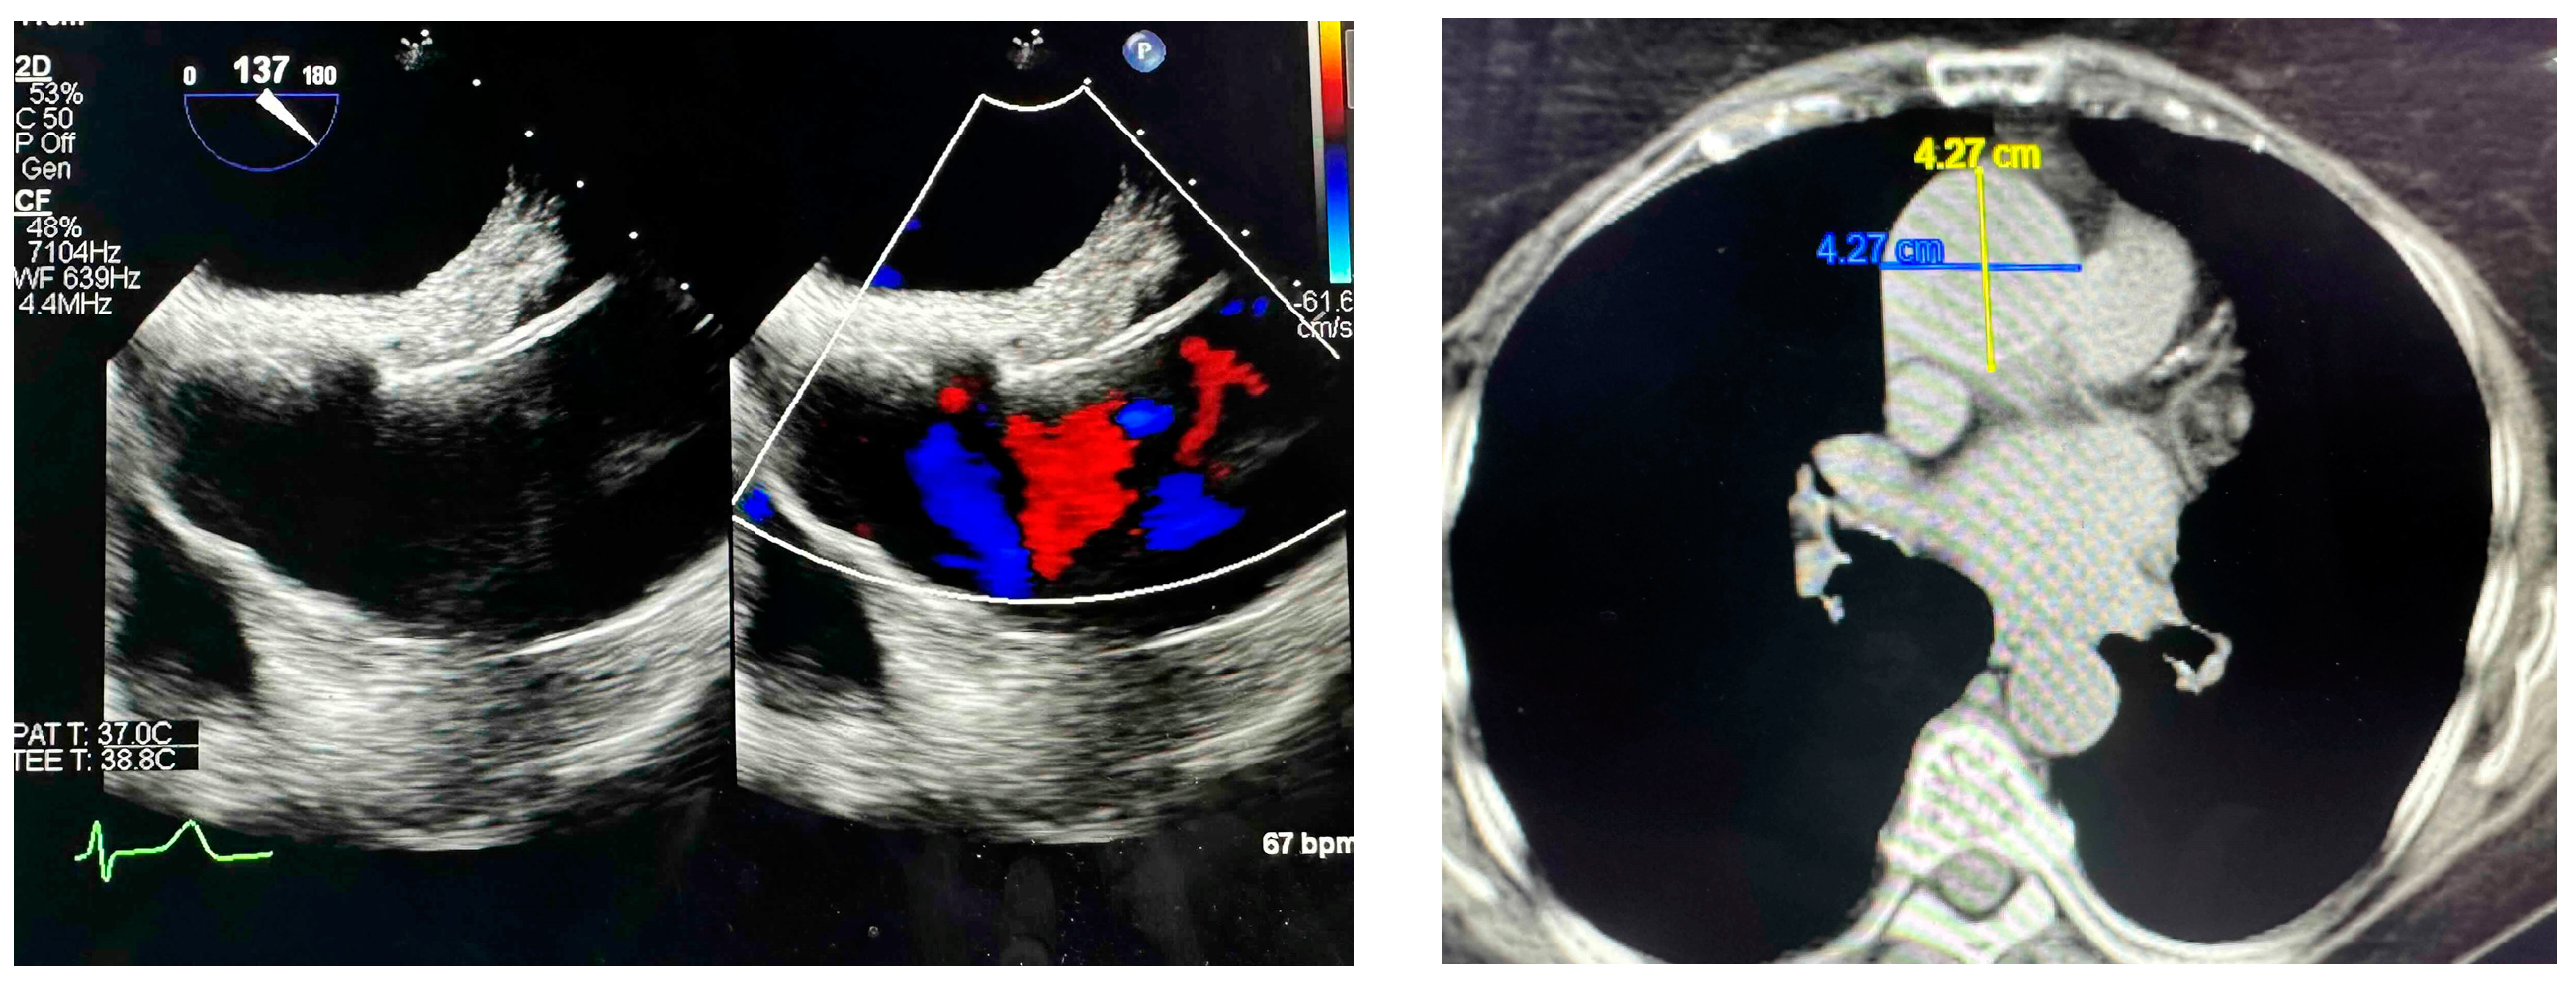

2.1.2. Subject 2—p.G1933V: ACGM Classification Variant of Unknown Significance